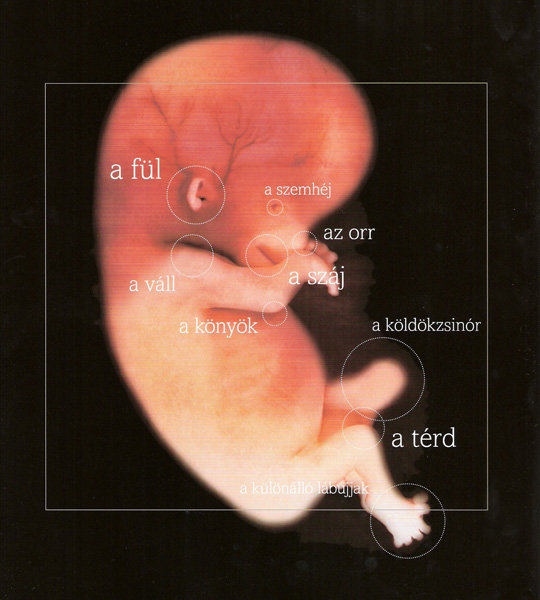

Annus nagyon jók a képek. kis ALien-nek néznek ki... szép az élet...

11 mm a baba  18 mm a baba

18 mm a baba

30 mm a baba

30 mm a baba Bébike nagyításban és életnagyságban

Bébike nagyításban és életnagyságban